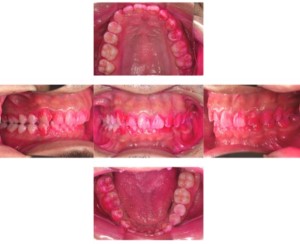

症例3

来院2回目、TBI後

症例

SRP後

初診時、TBI前

基本情報

年齢・性別 27歳・男性

主訴 主訴:左右下の歯ぐきに違和感がある

治療部位:全顎

治療内容 1.歯周基本検査、レントゲン撮影、口腔内写真、歯磨き指導、歯石除去、着色除去

2.SRP(スケーリングルートプレーニング)、再評価

その他

3.親知らずの抜歯

4.カリエス処置:右上1.2.3左上1.2.3右下6左下7CR(レジン充填)、右下7セラミックIn

5.定期検診

治療期間 6ヶ月

治療費 ※歯周基本治療の費用:PMTC以外保険診療3割負担

合計:19,680円

1.初診検査(歯周ポケット検査.レントゲン撮影):3,010円

2.歯磨き指導、歯面の歯石除去:1,410円

3.PMTC(自由診療):5,500円

4.SRP(歯周ポケット内の歯石除去)×4回:約2,000円/回

5.再評価:1,760円

(2023年12月現在)

リスク・副作用 ・最初は歯磨きをすると歯ぐきから出血するが毎日ホームケアを続けることで出血が徐々になくなる

・歯ぐきが腫れている状態が改善されると歯ぐきが引き締まり退縮するため、歯ぐきが下がったように感じることがある

・歯ぐきが引き締まると歯間が開いたように感じることがある

・歯ぐきが引き締まると知覚過敏の症状がでる可能性がある

・一度歯石を除去しても毎日のホームケアを怠ると再度歯石がつく

・治療後も再発を防ぐために定期的なメインテナンスが必要である

治療方針 1.初診検査(レントゲン撮影、口腔内写真、歯周検査、歯磨き指導)

2.歯磨きチェック、歯石除去、PMTC

3.SRP

4.再評価

特記事項 ・歯科医院は今回初めて

・タバコは24歳まで3年ほど吸っていたが健康のためにやめた

・親知らずは右下以外抜歯

・歯ブラシはルシェロP20M、補助用具はフロスを処方

担当者所見 全体的に歯と歯ぐきの境目に歯垢(細菌の塊)が残り、日々のホームケアで落とし切れていなかったことと、歯科医院への定期検診の習慣がなかったことから、全顎的な歯肉炎になってしまったと考えられる。

歯周基本治療とホームケアで歯ぐきの腫れや歯周ポケット、出血率などかなり改善されたが、出血がまだ0%ではない為、引き続き歯ブラシの当て方をお伝えしつつ今後は定期検診で3ヶ月おきに再発しないよう一緒に管理していく。